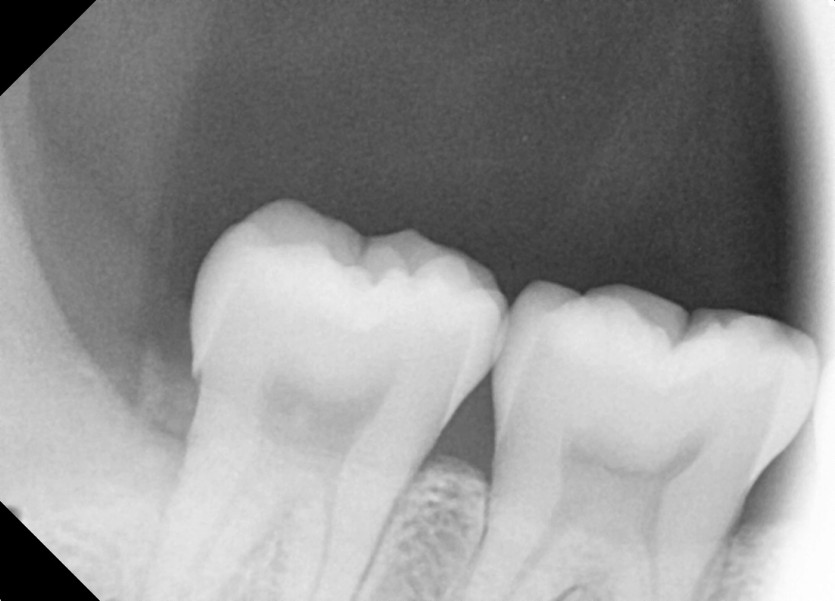

#18,48 사랑니 발치

구강 외과 전문의가 당일 발치했습니다.